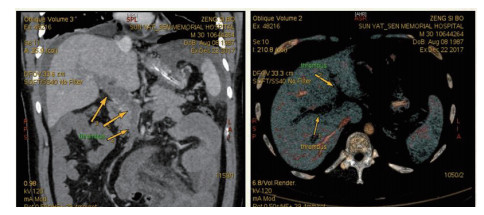

1 资料与方法患者男,30岁,因“腹胀、腹痛6 d,高热1 d”于2017年12月11日由广州南沙区中心医院转诊收入中山大学孙逸仙纪念医院全科医学科。患者本次起病前无明确病因或明显诱因。患者以左上腹轻微胀痛起病,进行性加重。南沙区医院查血常规:白细胞14.27×109/L,血小板50×109/L,中性粒细胞比例74.5%,嗜酸粒细胞1.02×109/L,嗜酸粒细胞比例7.2%。全腹CT+CTA提示:门静脉左右主干及其小分支栓子形成。后在3 d内连续复查血常规,提示血小板进行性下降,由50×109/L相继降至35×109/L、18×109/L;(嗜酸粒细胞计数及比例未能提供),并出现高热(体温39.5℃),因病情危重,遂转诊本院。入院时患者精神疲乏、高热,腹部胀痛难忍,伴有咳嗽。查体:体温38.6℃,心率87次/min,血压102/76 mmHg,指尖血氧饱和度90%~91%。双肺呼吸音粗,双肺均可闻及小水泡音。腹部稍膨隆,叩诊鼓音,左上腹及脐周轻压痛,无反跳痛。听诊肠鸣音减弱,约1~2次/min。当天查血常规示白细胞11.85×109/L,血小板23×109/L,中性粒细胞比例58.1%,嗜酸粒细胞3.5×109/L,嗜酸粒细胞比例29.5%。凝血常规提示:PT 15.9S,PTA 51.1%,PT/R 1.39,Fbg 1.59 g/L,PTINR 1.39,APTT 35.2 s,D-二聚体114.36 mg/L FEU(参考值范围0~0.55 mg/L FEU)。胸部+全腹部CT+CTA示“门静脉主干及左、右支、肠系膜上静脉近端栓子形成;腹主动脉及左侧髂总动脉小附壁血栓;左肺上叶尖后段、左肺上叶下舌段、右肺中叶及双肺下叶炎症;乙状结肠两段节段性管壁增厚,建议排外占位性病变;腹水、盆腔积液,大网膜炎性病变可能性大”。每日复查血常规,发现血小板进行性下降,最低至15×109/L(参考值范围125~350×109/L),嗜酸粒细胞计数及比例进行性升高,分别达到8.07×109/L(参考值范围0.020~0.52×109/L)和51.1%(参考值范围0.4-8.0%)。每日复查凝血常规亦提示凝血指标不断恶化,纤维蛋白原最低降至0.63 g/L。在予禁食、“美平(美罗培南)”抗感染、输注纤维蛋白原及血小板、维护水电解质平衡及营养支持的积极治疗的同时,还积极完善了以下检查寻找病因:①血液系统方面:血浆鱼精蛋白副凝实验:阳性(+);凝血功能实验:PT 15.5S↑,PTA 47.8%↓,PT/R 1.35↑,PTINR 1.36↑,APTT 40.4 s↑,AT-Ⅲ 57.7%↓,F-VII 32.8%↓,F-Ⅷ 68.1%↓,F-X 68.0%↓,F-XII 24.0%↓;纤维蛋白降解产物:381.4 mg/L↑;血栓弹力-血小板图:R时间10.3 min↑;角度18.5度↓;最大血块强度13.2 mm↓;MA(ADP)值5.6 mm↓。骨髓病理学:嗜酸性粒细胞增多(43%),巨核细胞减少(7个)。慢淋/淋巴瘤表型分析:获取和分析细胞数5.0万;粒细胞区百分比82.6%;淋巴细胞区百分比9.4%;单核细胞区百分比2.0%;CD45dim细胞区百分比1.3%;有核红及细胞碎片区域百分比4.6%。ETV6/PDGFRB融合基因、FIP1L1/PDGFRA融合基因(—)。骨髓细胞学病理结果:符合嗜酸细胞增多症;②消化系统检查:大便细菌培养鉴定及药敏提示无志贺、沙门菌生长,有真菌生长;大便难辨梭菌毒素检测(—);粪便找寄生虫、找阿米巴、寄生虫七项均为(—);消化肿瘤系列提示CA-125 244.8 U/mL↑;腹腔穿刺术穿出“血性腹水”,腹水CA-125 1006.0 U/mL↑,腹水找癌细胞(—);复查腹部CT+CTA:乙状结肠两段节段性管壁增厚,建议进一步检查;排外占位性病变;遂行PET-CT:提示全身未见明确恶性征象。行电子结肠镜示:内镜诊断:(1)回肠末段炎症;(2)乙状结肠炎症;(3)内痔。钳取组织送病理,提示:标本①(回肠末端)黏膜组织呈慢性炎,伴糜烂,一些嗜酸性粒细胞浸润(约35个/HPF);②(乙状结肠)黏膜组织呈慢性炎,伴糜烂,个别嗜酸性粒细胞浸润(约4个/HPF)。③风湿免疫系统方面:免疫八项、风湿四项:C反应蛋134.0 mg/L,余未见异常;总IgE 170 IU/mL↑;抗ENA抗体、狼疮两项、血管炎两项、免疫球蛋白G4、抗心磷脂抗体三项均为阴性;④其他感染病原学检查:乙肝、肝炎系列、性病三项、痰找抗酸杆菌、T-spot实验、流行性出血热、登革热抗体、登革热病毒NS1抗原、外斐氏试验、肥达氏试验、痰结核培养、骨髓培养、血液细菌、血液厌氧菌培养均为阴性。经过上述检查,初步考虑“特发性嗜酸性细胞增多症”,于12.15开始予“甲泼尼松龙40 mg静滴, 1次/d”及“低分子肝素0.6 ml皮下注射, 1次/d”抗炎抗凝治疗。患者病情及检验指标有所好转,热退、腹胀减轻,血常规提示血小板升至49 ×109/L,嗜酸粒细胞计数和比例均下降至正常,凝血常规提示D-二聚体降至47.90 mg/L FEU。但12-22患者自行进食多量米饭后突发腹胀痛较前加重,急查血常规提示白细胞升至21×109/L,血小板再次下降至15×109/L,D-二聚体升至97.28 mg/L FEU,全腹CTA提示“门静脉主干及左、右支、肠系膜上静脉近端新发栓子形成”,遂于当日转至ICU予“尿激酶20万U+肝素钠1250 U”溶栓治疗后予“低分子肝素0.6 ml皮下注射, 1次/12 h”序贯抗凝治疗。后患者病情渐渐稳定,至2018-1-18患者在“甲泼尼松龙12 mg口服, 1次/d”及“立伐沙班20 mg口服, 1次/d”的维持治疗下,血小板、嗜酸粒细胞计数及纤维蛋白原均回复正常,D-二聚体下降至3.52 mg/L FEU。但遗憾的是,此时患者再次进食大量米饭,约1 h后突发腹痛、气促,急行胸片+腹平片提示:“双侧膈下游离气体,考虑胃肠道穿孔可能;双下肺少许炎症,少量胸腔积液;腹部多量积气伴肠腔扩张”。遂即送手术室行全麻下“腹腔镜探查+坏死空肠切除+大网膜切除+肠系膜上动脉探查+空回肠双腔造口术”,术后病理提示标本①(大网膜)脂肪组织,部分坏死,合并慢性炎,伴一些中性粒细胞浸润,较多泡沫样组织增生,未见明确血栓,未见恶性改变。②(部分空肠)肠壁组织,部分肠壁全层坏死,合并慢性炎,肉芽组织增生,未见明确血栓,未见恶性改变。免疫组织化学:CD38浆细胞(+)、IgG(+)、IgG4(﹣)。术后继续予“立伐沙班10 mg/d”和“甲泼尼松龙8 mg/d”口服治疗,并于2018.2.4停用“甲泼尼松龙”。2.28复查全腹CTA,仍可见“脾静脉新发血栓,门静脉及肠系膜上静脉血栓较前好转”。3.20行空回肠双腔造瘘管泛影葡胺造影术提示“双腔造瘘管通畅,右中下腹小肠蠕动尚可,结肠各段及直肠通畅,未见对比剂外漏征象”。但患者合并了严重的短肠综合征,致严重低钾低钠血症和继发的代谢性脑病,病情再度转危。继续纠正电解质紊乱、补充营养,最终病情好转后于4.11行“造瘘口回纳修补术”。随访半年,患者仍口服“立伐沙班10 mg/d”抗凝治疗,复查血常规、凝血常规等各项指标均正常,但营养状况较差。

| 图 1 全腹CTA(2017-12-22):门静脉及肠系膜上静脉血栓形成 |